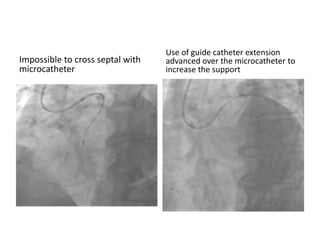

Proximal RCA CTO

J CTO 3 (Second attempt,> 20mm,>45°)

Retrograde approach

Septal Surfing with Sion

Impossible to cross septal with

microcatheter

Use of guide catheter extension

advanced over the microcatheter to

increase the support

Septal crossing with microcatheter

allowed by extension guide catheter

support

Antegrade wire positionned to allow

Reverse Cart

• Final result